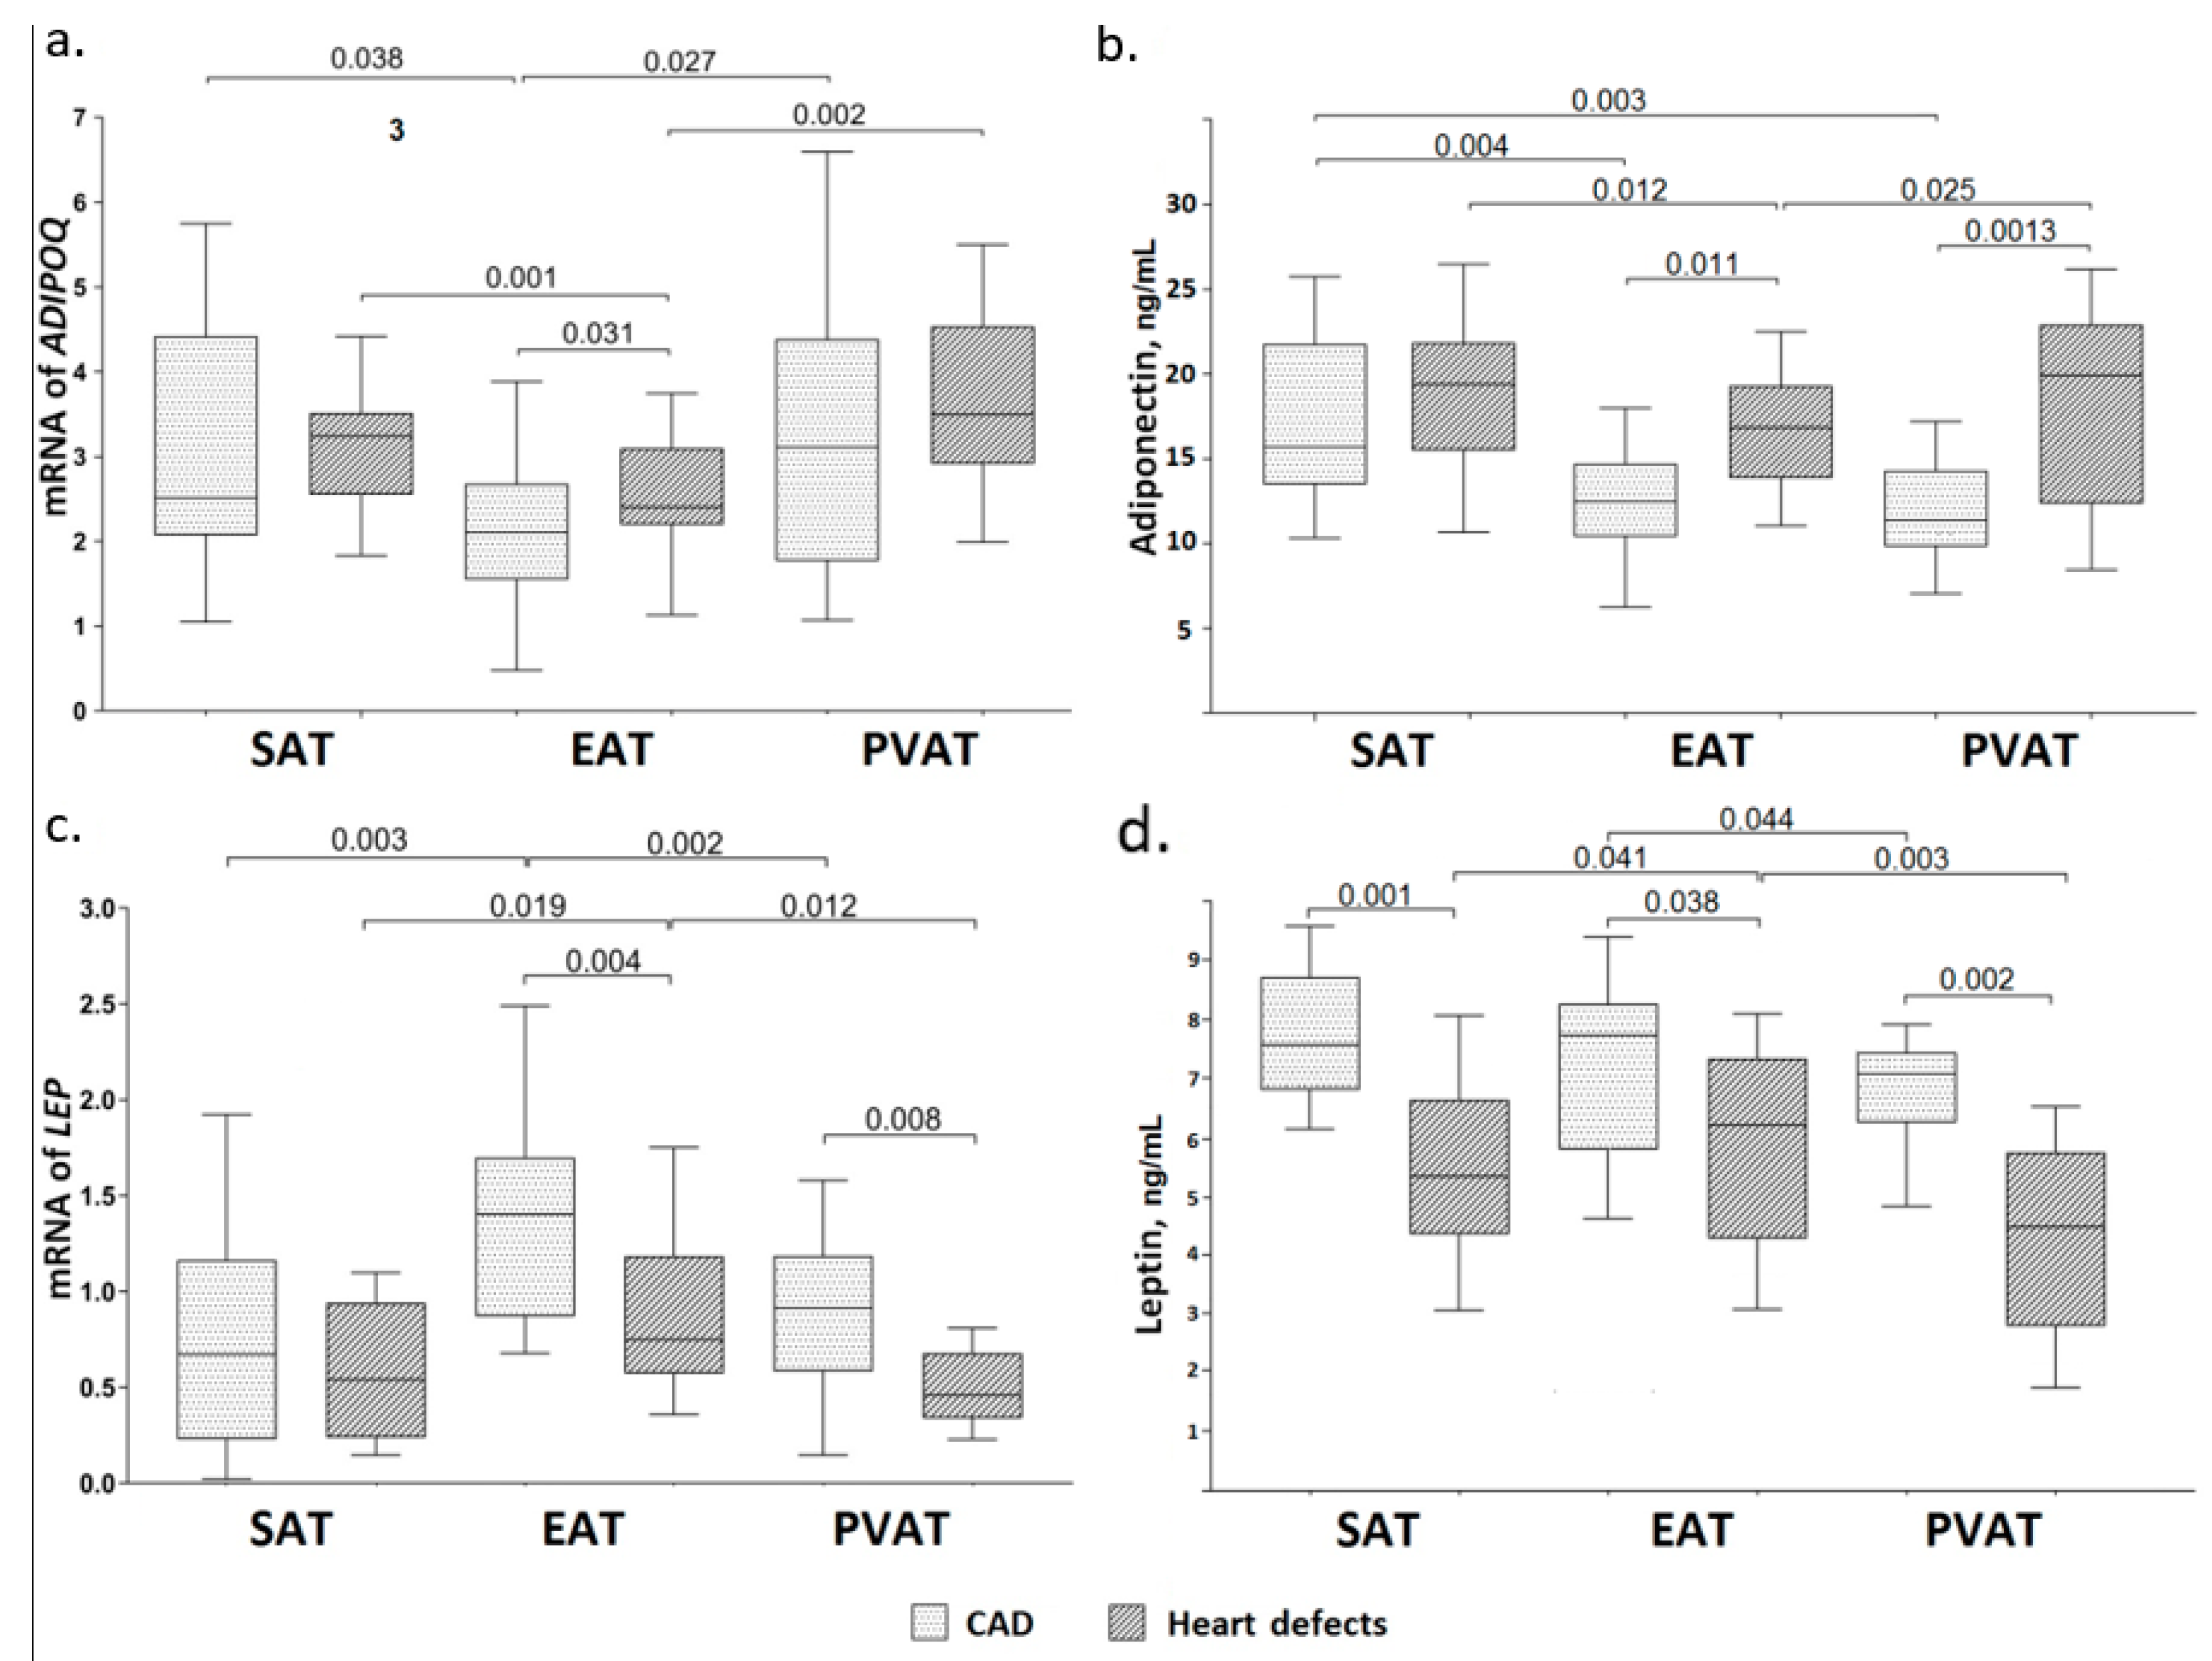

3.2. Adiponectin Gene Expression and Concentration of Adiponectin in the Daily Adipocyte Culture of Various Fat Depots

3.3. Leptin Gene Expression and Concentration of Leptin in the Daily Adipocyte Culture of Various Fat Depots